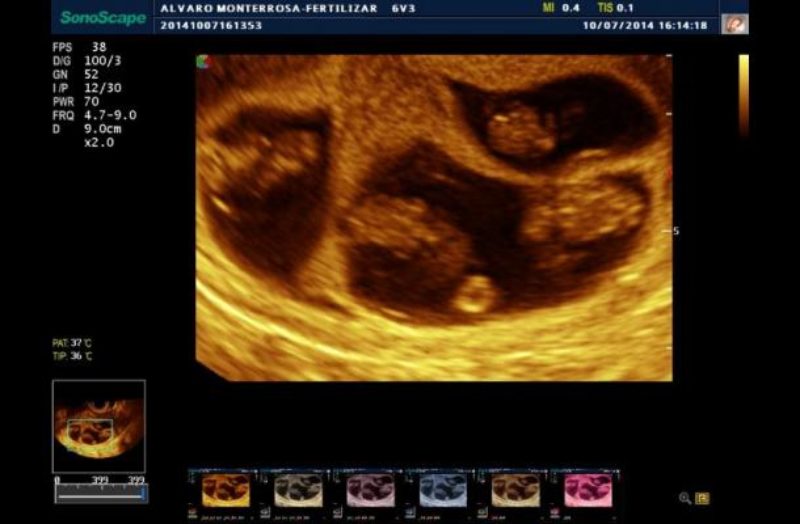

Hospital Quirón Zaragoza reduce al 5% las probabilidades de embarazo gemelar en fecundación in vitro

• La Unidad de Reproducción Asistida ha incorporado el test Eeva, que permite detectar qué embriones tienen mayor capacidad para generar un embarazo, aumentando las posibilidades de éxito de la FIV y disminuyendo el riesgo de embarazo múltiple.

• En Aragón, veinte de cada cien parejas que se realizan una fecundación in vitro tienen gemelos